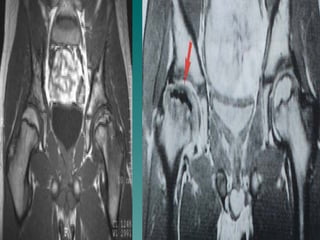

Manyetik Rezonans Görüntüleme

 MR  osteonekrozu erken devresinde

görüntüleyerek tanıyı kolaylaştırır ve

artiküler kıkırdağın sınırlarını net bir

şekilde gösterir.

 Infarktı göstermede çok sensitiftir,

ama iyileşme devrelerini doğru

sınırlar ile ayırmada henüz yeterli

değildir.

 Hastalığın tedavi takibindeki yeri

henüz netleşmemiştir.

Manyetik Rezonans Görüntüleme MR osteonekrozu erken devresinde görüntüleyerek tanıyı kolaylaştırır ve artiküler kıkırdağın sınırlarını net bir şekilde gösterir.  Infarktı göstermede çok sensitiftir, ama iyileşme devrelerini doğru sınırlar ile ayırmada henüz yeterli değildir.  Hastalığın tedavi takibindeki yeri henüz netleşmemiştir.